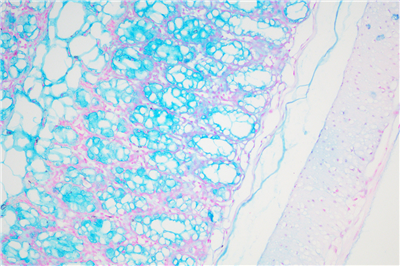

阿利新藍的染色原理在于是類銅鈦花青染料,這種陽離子染料與酸性基團結合,也即阿利新藍與組織內含有的陰離子基團如羧基和硫酸根形成不溶性復合物。分子中帶正電荷的鹽鍵與酸性粘多糖物質中帶負電荷的酸性集團結合形成不溶性的復合物而呈藍色,